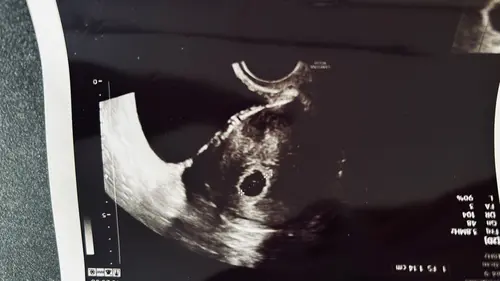

Mein erster Termin sollte eigentlich am 8.8 sein. Jetzt musste ich gestern hin weil ich eine Blutung hatte 😔 man hat leider nur fruchthöhle gesehen. HCG hat sich aber von Dienstag auf Donnerstag verdoppelt 🍀

Ich hoffe das man Donnerstag mehr sieht 🍀🐝 drückt mir die Daumen 🍀

Das warten ist wirklich das schlimmste

Man hat einen wunderschönen Dottersack gesehen 🐝🍀♥️

Nächste Woche Donnerstag geht wieder hin und dann bekomme ich den Mutterpass 🤭